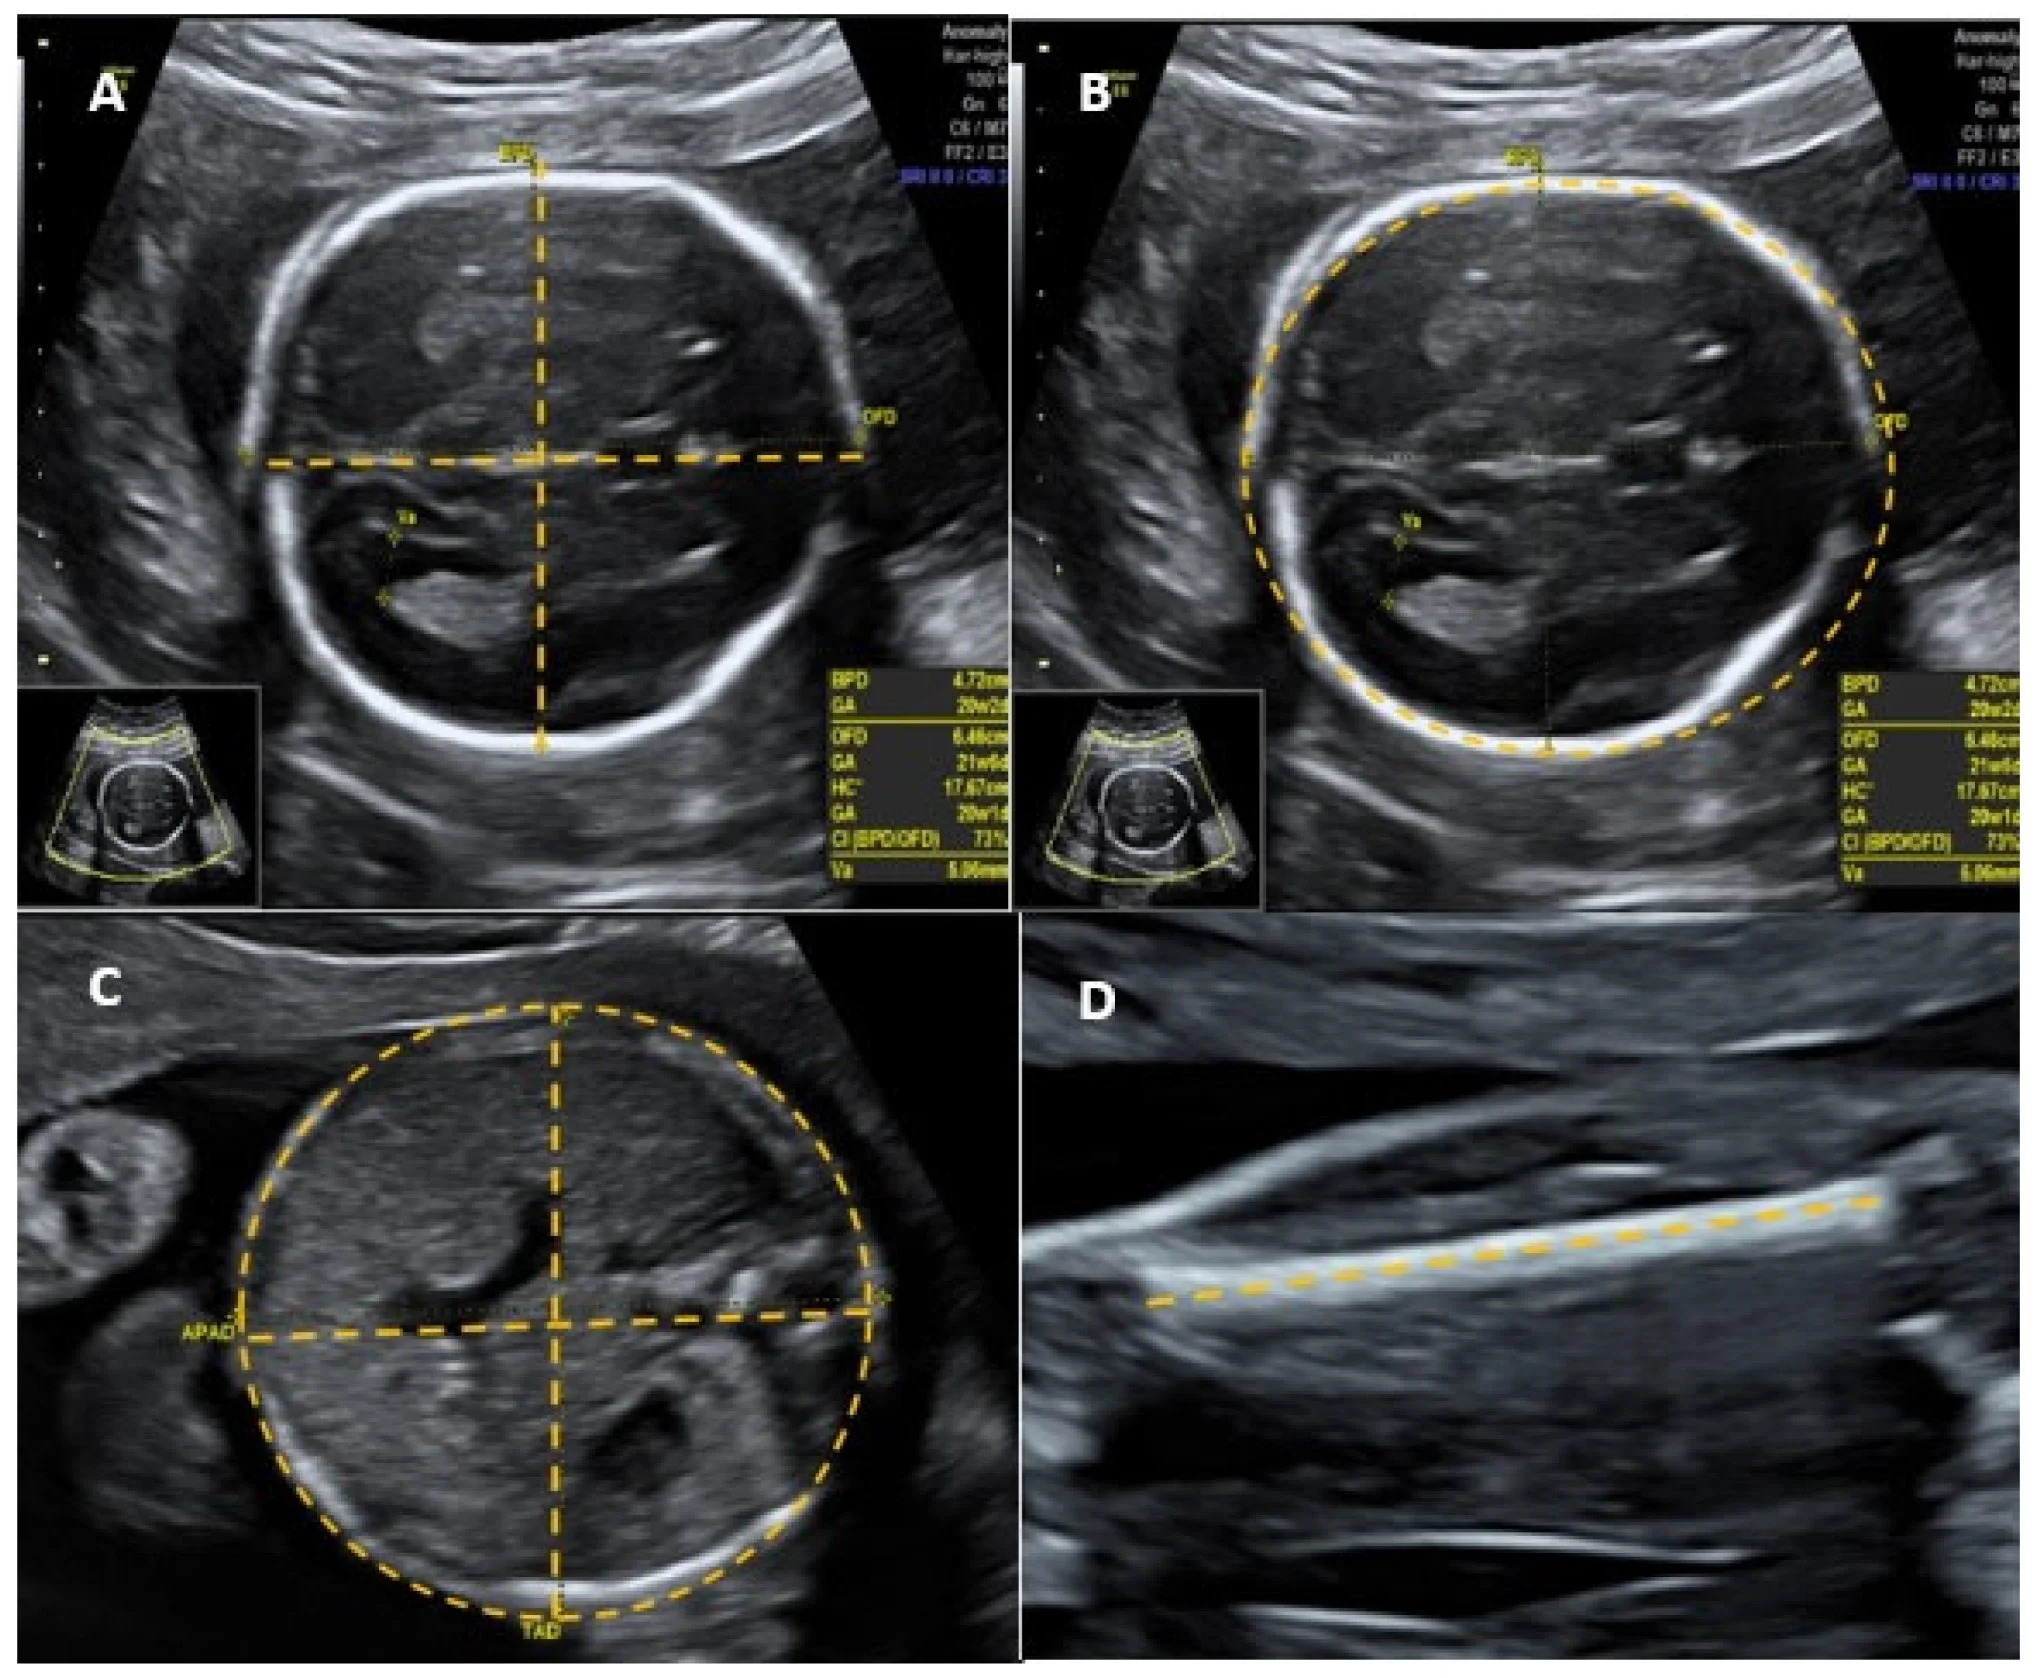

Ultrasound Images of a Fetal Head

- Fetal biometry: biparietal diameter (BPD), head circumference, abdominal circumference, femoral length, calculated fetal weight.

- Abdominal circumference is the single most effective parameter for predicting fetal weight. Z